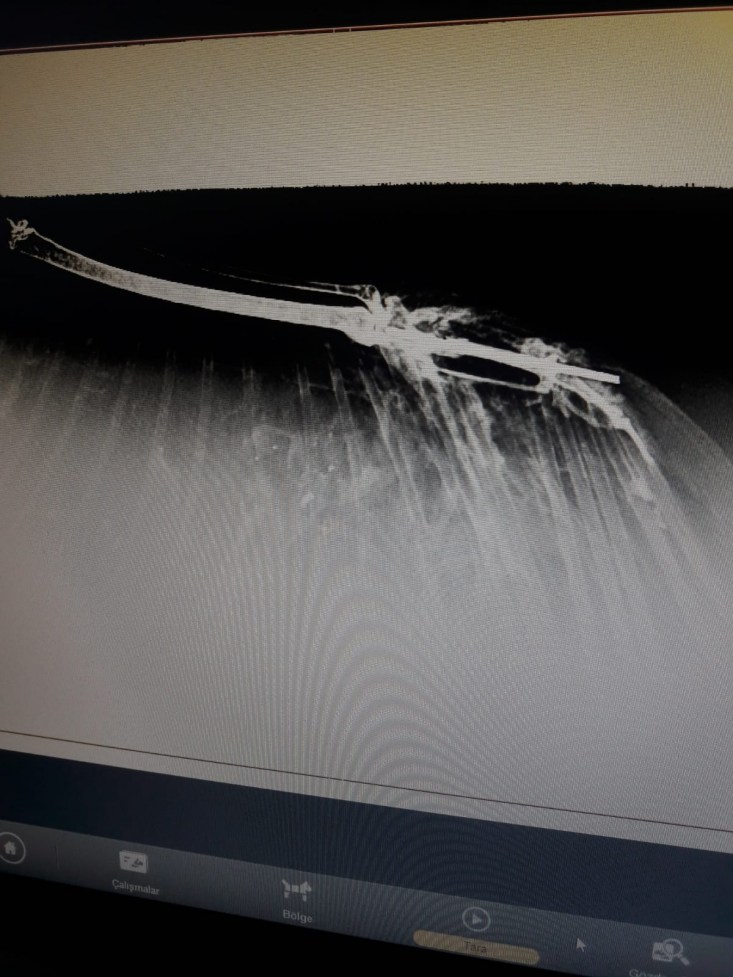

yapılmak üzere ERVET veteriner hekimliğine getirildi. Saçmalardan dolayı

kanatlarında ve kemiklerde kırılmalar meydana gelen Doğan kuşları çekilen

röntgenin ardından tedavilerine başlandı.

tarafından getirildi bu kuşumuz. Önce röntgenini çektik. Röntgeninde kemiğinin

saçma ile parçalandığını, darmadağınına yakın bir parçalanma yaşamış kemiği.

Pazar günü bunu operasyona aldık. Kırık kemiğinin parçalarını düzelttik. Kalan

kemiklerin arasındaki bağlantıyı sağladık. Önce tabi şoka giriyorlar bu durum